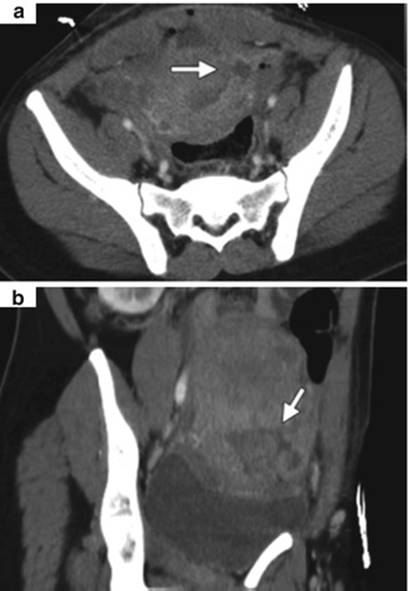

16.7.2 Abdominal CT

Abdominal CT scan should be done in unequivocal cases such as intestinal adhesions over uterine rupture delaying diagnosis. It is seen as focal disruption of the myometrium along with hemoperitoneum (Fig. 16.9). Other signs (see direct and indirect signs) such as fetal parts or hemoperitoneum outside of the uterus can be seen (Figs. 16.10, 16.11 and 16.12).

Fig. 16.9

Partial uterine rupture in a 29-year-old woman. Axial (a) and coronal oblique (b) contrast-enhanced CT images obtained 4 days after Cesarean delivery show disruption of the myometrium (arrow) in the left side of the lower uterine segment, a finding depicted as a hypoattenuating band in the myometrium connecting the uterine cavity with a fluid collection in the left broad ligament and pelvis [208]

Fig. 16.12

A 34-year-old woman with seven previous Cesarean deliveries and a history of scant prenatal care presented at 32 weeks. The CT scan revealed a fetal hand protruding through the lower uterine segment (arrow) [210]